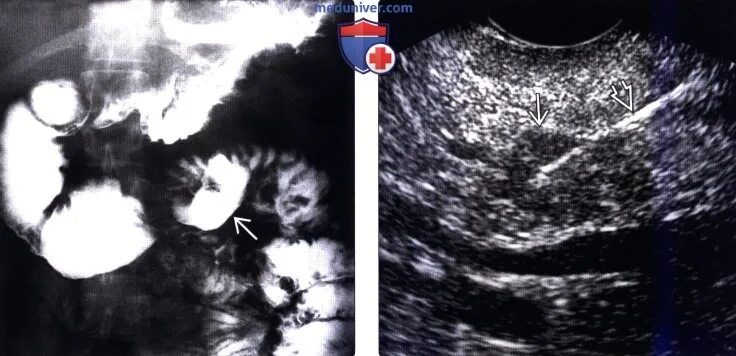

Симптом золлингера эллисона что это